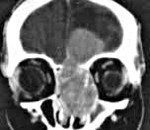

Эстезионейробластома может быть обнаружена по данным рентгенографии околоносовых пазух. Более информативными методами являются КТ носовых пазух и МРТ головного мозга, дающие исчерпывающую информацию о размерах опухоли и границах ее распространения. В 70-50% случаев эстезионейробластомы опухолевые клетки обнаруживаются при цитологическом анализе носового отделяемого. Однако их отсутствие в мазке не позволяет исключить опухоль. Окончательно верифицировать диагноз «Эстезионейробластома» возможно только по результатам гистологического исследования тканей новообразования, взятых путем биопсии в ходе риноскопии.

Поиск регионарных и отдаленных метастазов эстезионейробластомы проводится с использованием КТ глотки, УЗИ тканей шеи, сцинтиграфии скелета, КТ грудной клетки, МРТ печени и МСКТ брюшной полости.